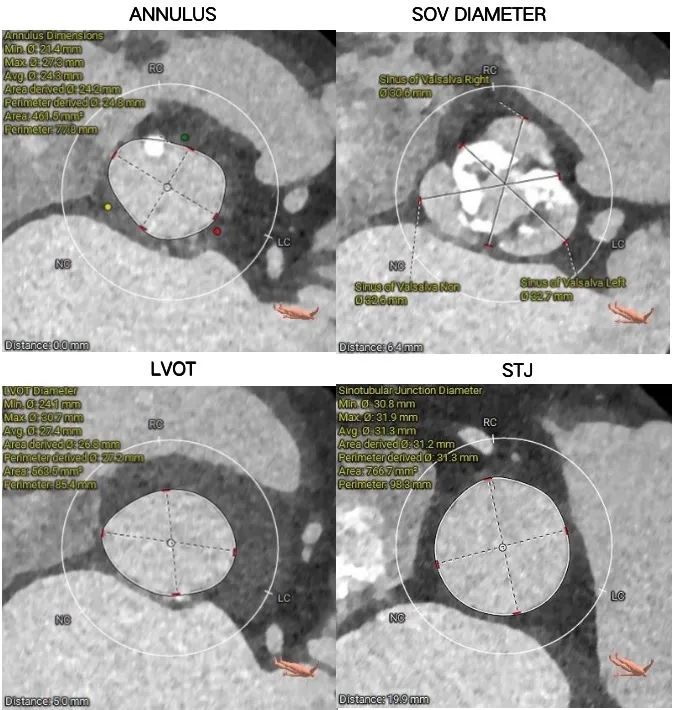

主动脉根部测量

1.Type 2型二叶式主动脉瓣重度钙化,左窦和右窦、右窦和无窦瓣叶对合缘处存在钙化嵴,左室流出道呈敞口形态,瓣膜锚定难度适中,瓣膜植入受二叶瓣瓣叶及钙化挤压存在移位及少量偏多瓣周漏风险。

2.左冠脉开口高度偏低,左冠切线角度测量瓣叶大于LCA开口下缘到根部距离,结合瓦氏窦及STJ尺寸预估,冠脉风险增高。

4.预装AV23瓣膜,释放角度·RAO·3·° ·CAU·23(左右重合)左右,瓣环下零位开始释放,建议释放后调整至左冠切线位 ·LAO·35·° CRA·12· 左右进一步确定冠脉冠灌注及人工瓣膜展开形态,瓣膜释放过程操作难度适中,要求团队密切配合,充分利用瓣膜系统部分及完全回收功能。